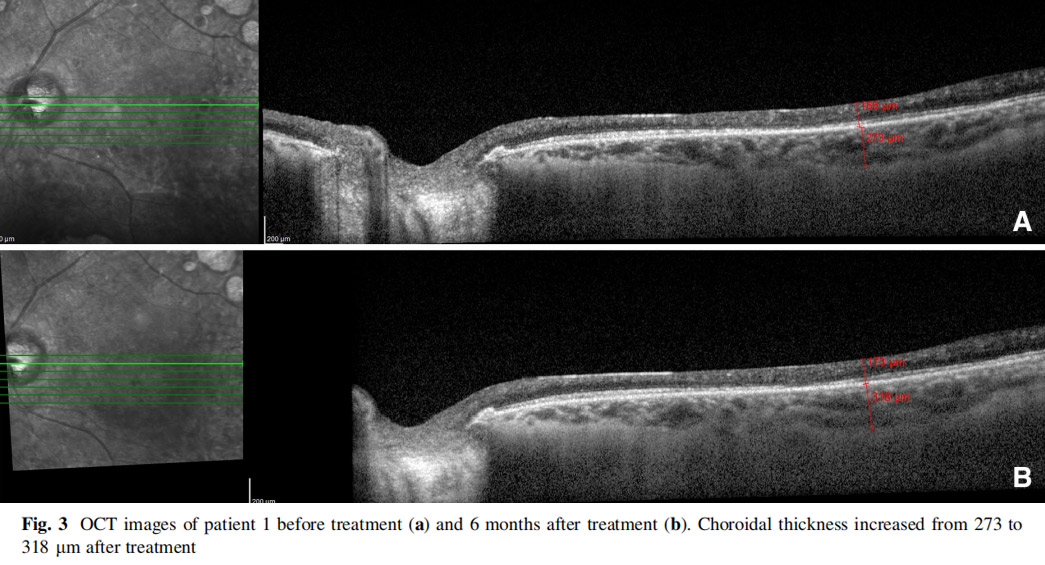

患者左眼接受AD-MSCs治療,6個月后視力提高至2米處數(shù)手指(CF)水平,視野中央島狀結(jié)構(gòu)擴大,如圖1所示,左眼mfERG顯示改善(圖2),脈絡(luò)膜厚度從273μm增加至318μm(圖3),黃斑厚度和RNFL沒有變化。